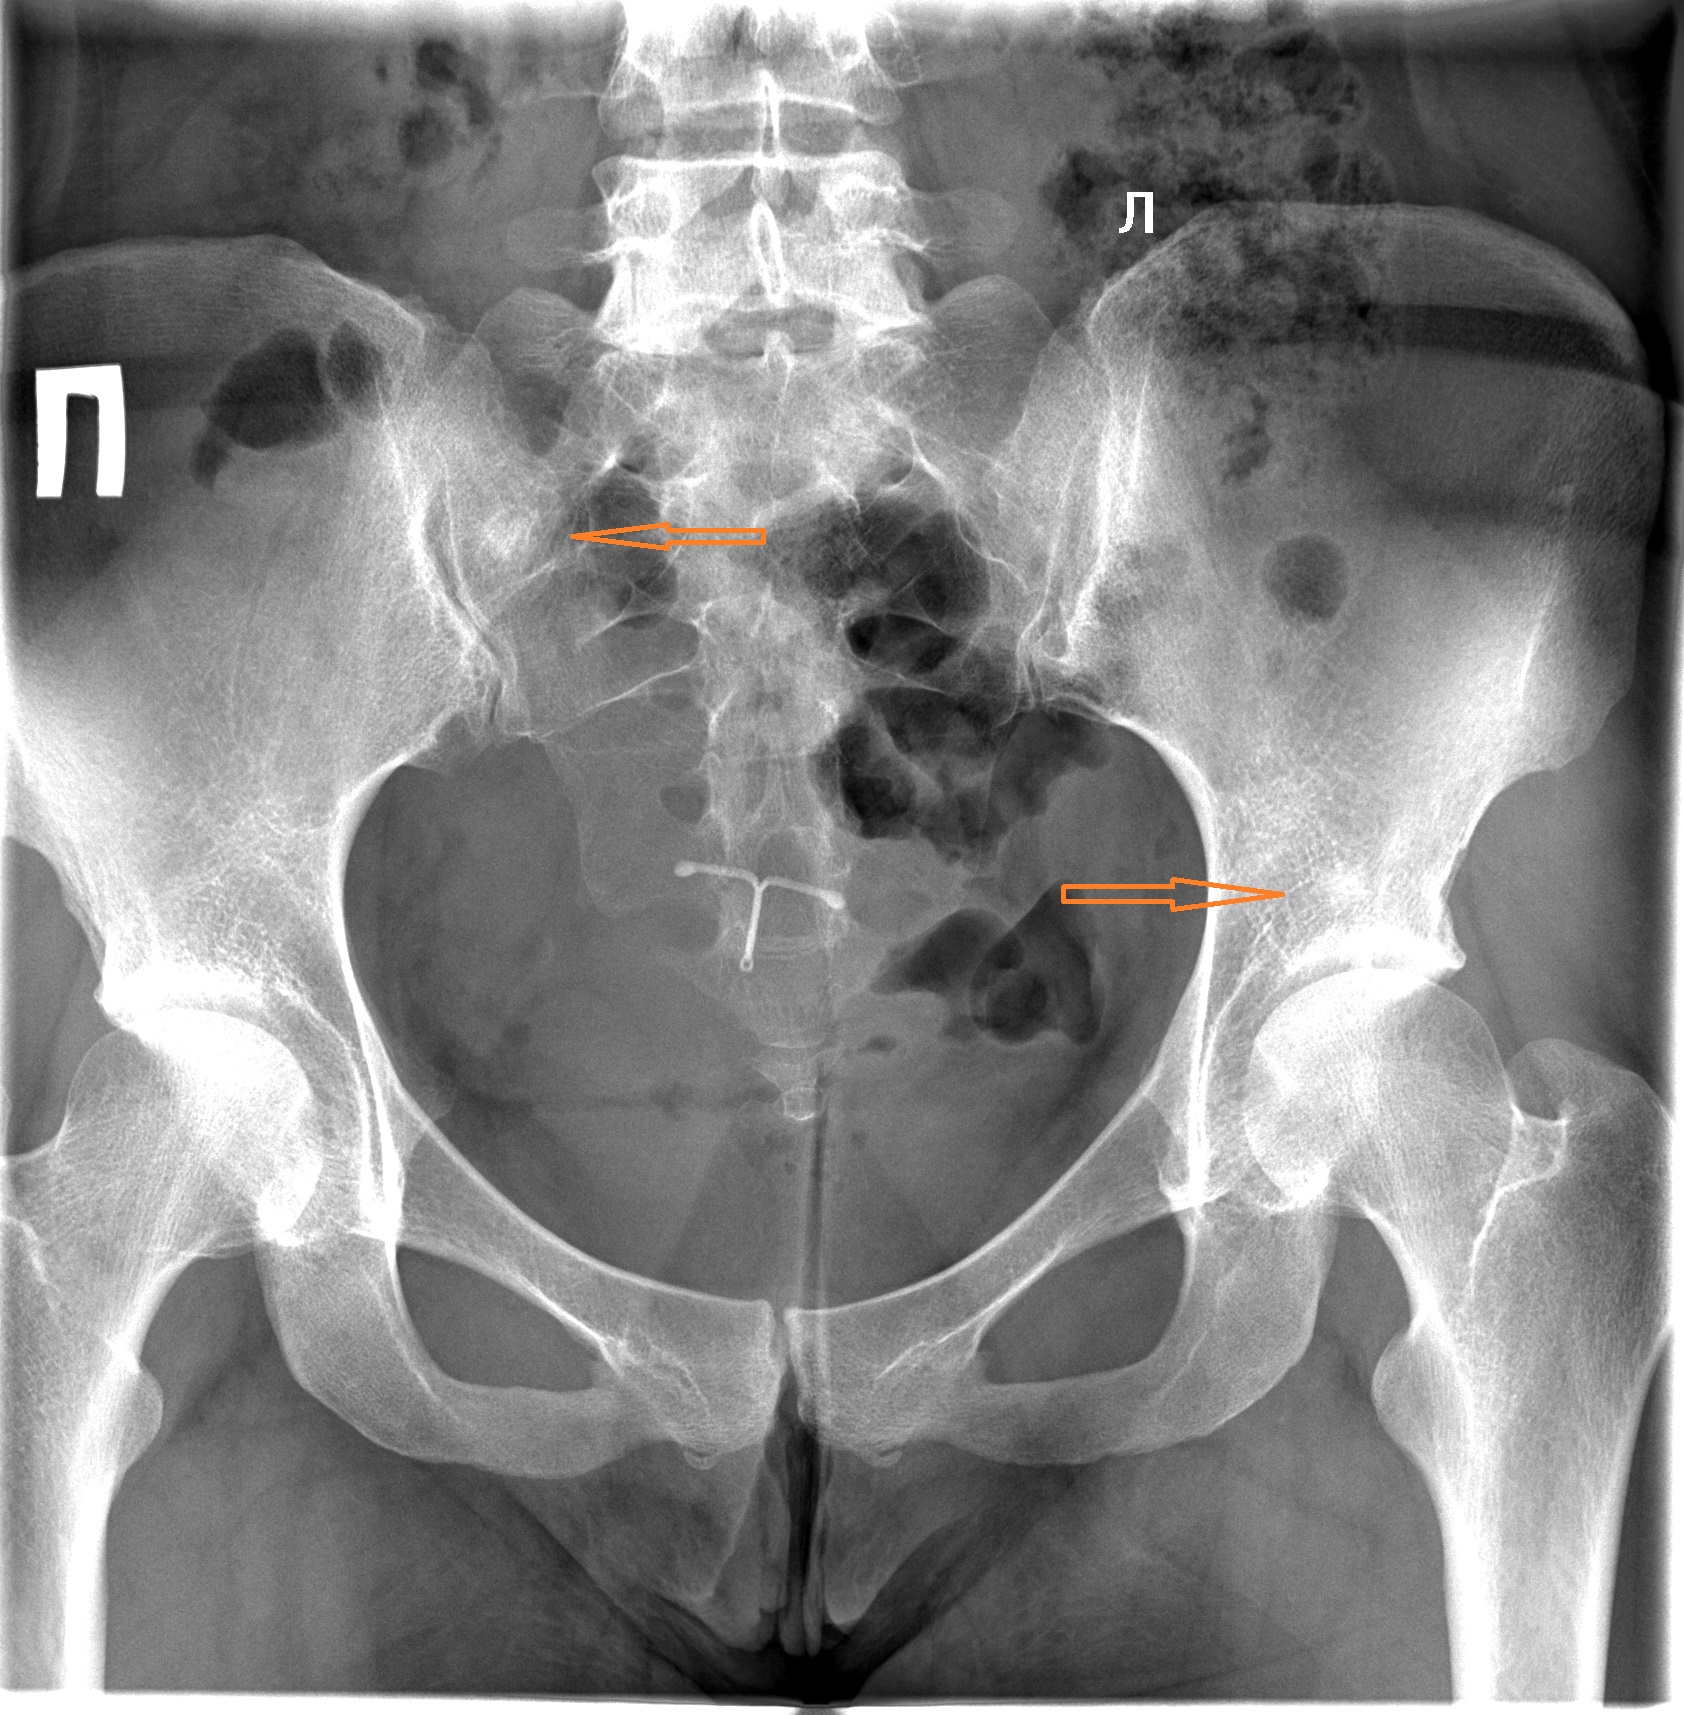

Рентгеновские снимки крестцово-копчикового отдела позвоночника